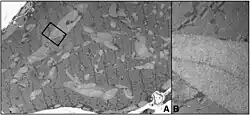

Glycogen deposits in the muscle of a human patient, shown by electron microscopy. The presence of this excess glycogen in muscle tissue is a result of phosphofructokinase deficiency.[18]

A diagnosis can be made through a muscle biopsy that shows excess glycogen accumulation. Glycogen deposits in the muscle are a result of the interruption of normal glucose breakdown that regulates the breakdown of glycogen. Blood tests are conducted to measure the activity of phosphofructokinase, which would be lower in a patient with this condition.[19] Patients also commonly display elevated levels of creatine kinase.[7]